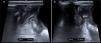

A boy aged 3 years presented with intermittent abdominal pain of 72hours duration, fever of 3hours duration and self-limited vomiting associated with episodes of crying, drawing legs to chest and diaphoresis. There was diffuse tenderness in the abdomen and the physical examination was difficult. The ultrasound was not very useful due to poor cooperation, as it was not possible to identify the appendix or assess for inflammatory signs. Blood tests revealed leukocytosis (20500/mm3) with a procalcitonin (PCT) level of 0.5ng/mL and a C-reactive protein (CRP) level of 61mg/L. Given the abdominal pain of undetermined aetiology and the inability to rule out a condition requiring surgery, the patient was admitted for observation. Since the symptoms persisted, the tests were repeated at 14hours, evincing a decrease in the white blood cell count (19100) and the level of PCT (0.3), albeit mild, and further elevation of CPR (69). A new ultrasound scan evinced an appendix measuring up to 11mm (Fig. 1), and surgery evinced the presence of a nonpurulent appendiceal phlegmon with torsion of the appendix, which was removed. Fig. 2 shows the surgical specimen and Fig. 3 an illustration of its examination. The postoperative outcome was favourable and the patient was discharged 5 days after the procedure.